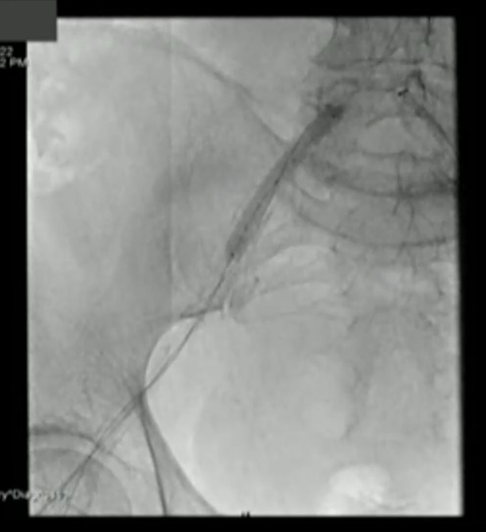

来自丹麦 Copenhagen University Hospital的Ole De Backer教授分享了一例IVL辅助经股动脉经导管主动脉瓣置入冲击钙化的案例。患者为77岁男性,严重主动脉瓣钙化狭窄,置入双腔起搏器。检查显示该患者髂动脉多处出现血管钙化,无法满足经股动脉入路的TAVI。鉴于此,Ole De Backer教授根据CT钙化评分后,采用Shockwave M5+,7mm*60mm球囊对髂动脉血管钙化区域进行治疗,治疗后血管管腔充分获得扩张,钙化组织得到修饰,为后续手术提供了通畅的入路(如图10,11)。最后,他总结道,根据后期随访显示,提前应用IVL对股动脉进行疏通,能够有效降低TF-TAVI术后发生不良心血管临床事件的风险,且患者预后效果更好。

图片

图10

图11